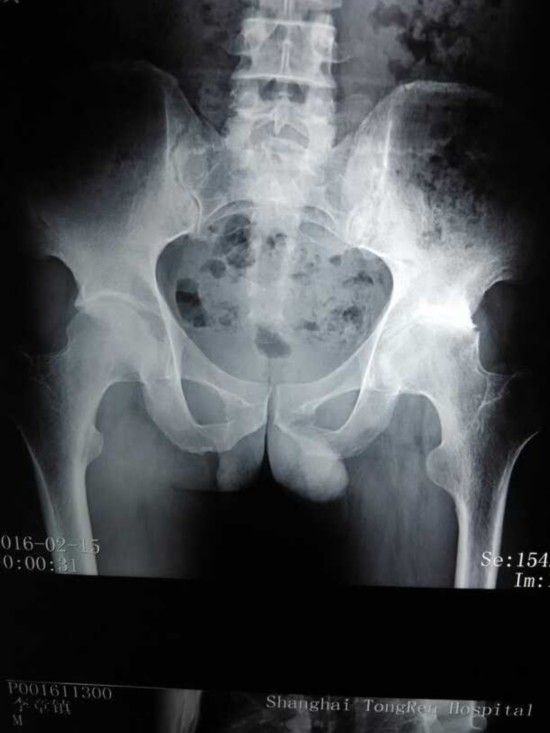

专家好,我是强直性脊柱炎患者,主要受累是髋关节,请看照片。问:我髋关节可以保守治疗吗?请给我一个治疗方案,谢谢。

王朝鲁主任:由于片子没有标出左右,只能看出一侧髋关节重度骨关节炎,保守治疗效果比较差,根据年龄情况建议尽早进行髋关节置换术。